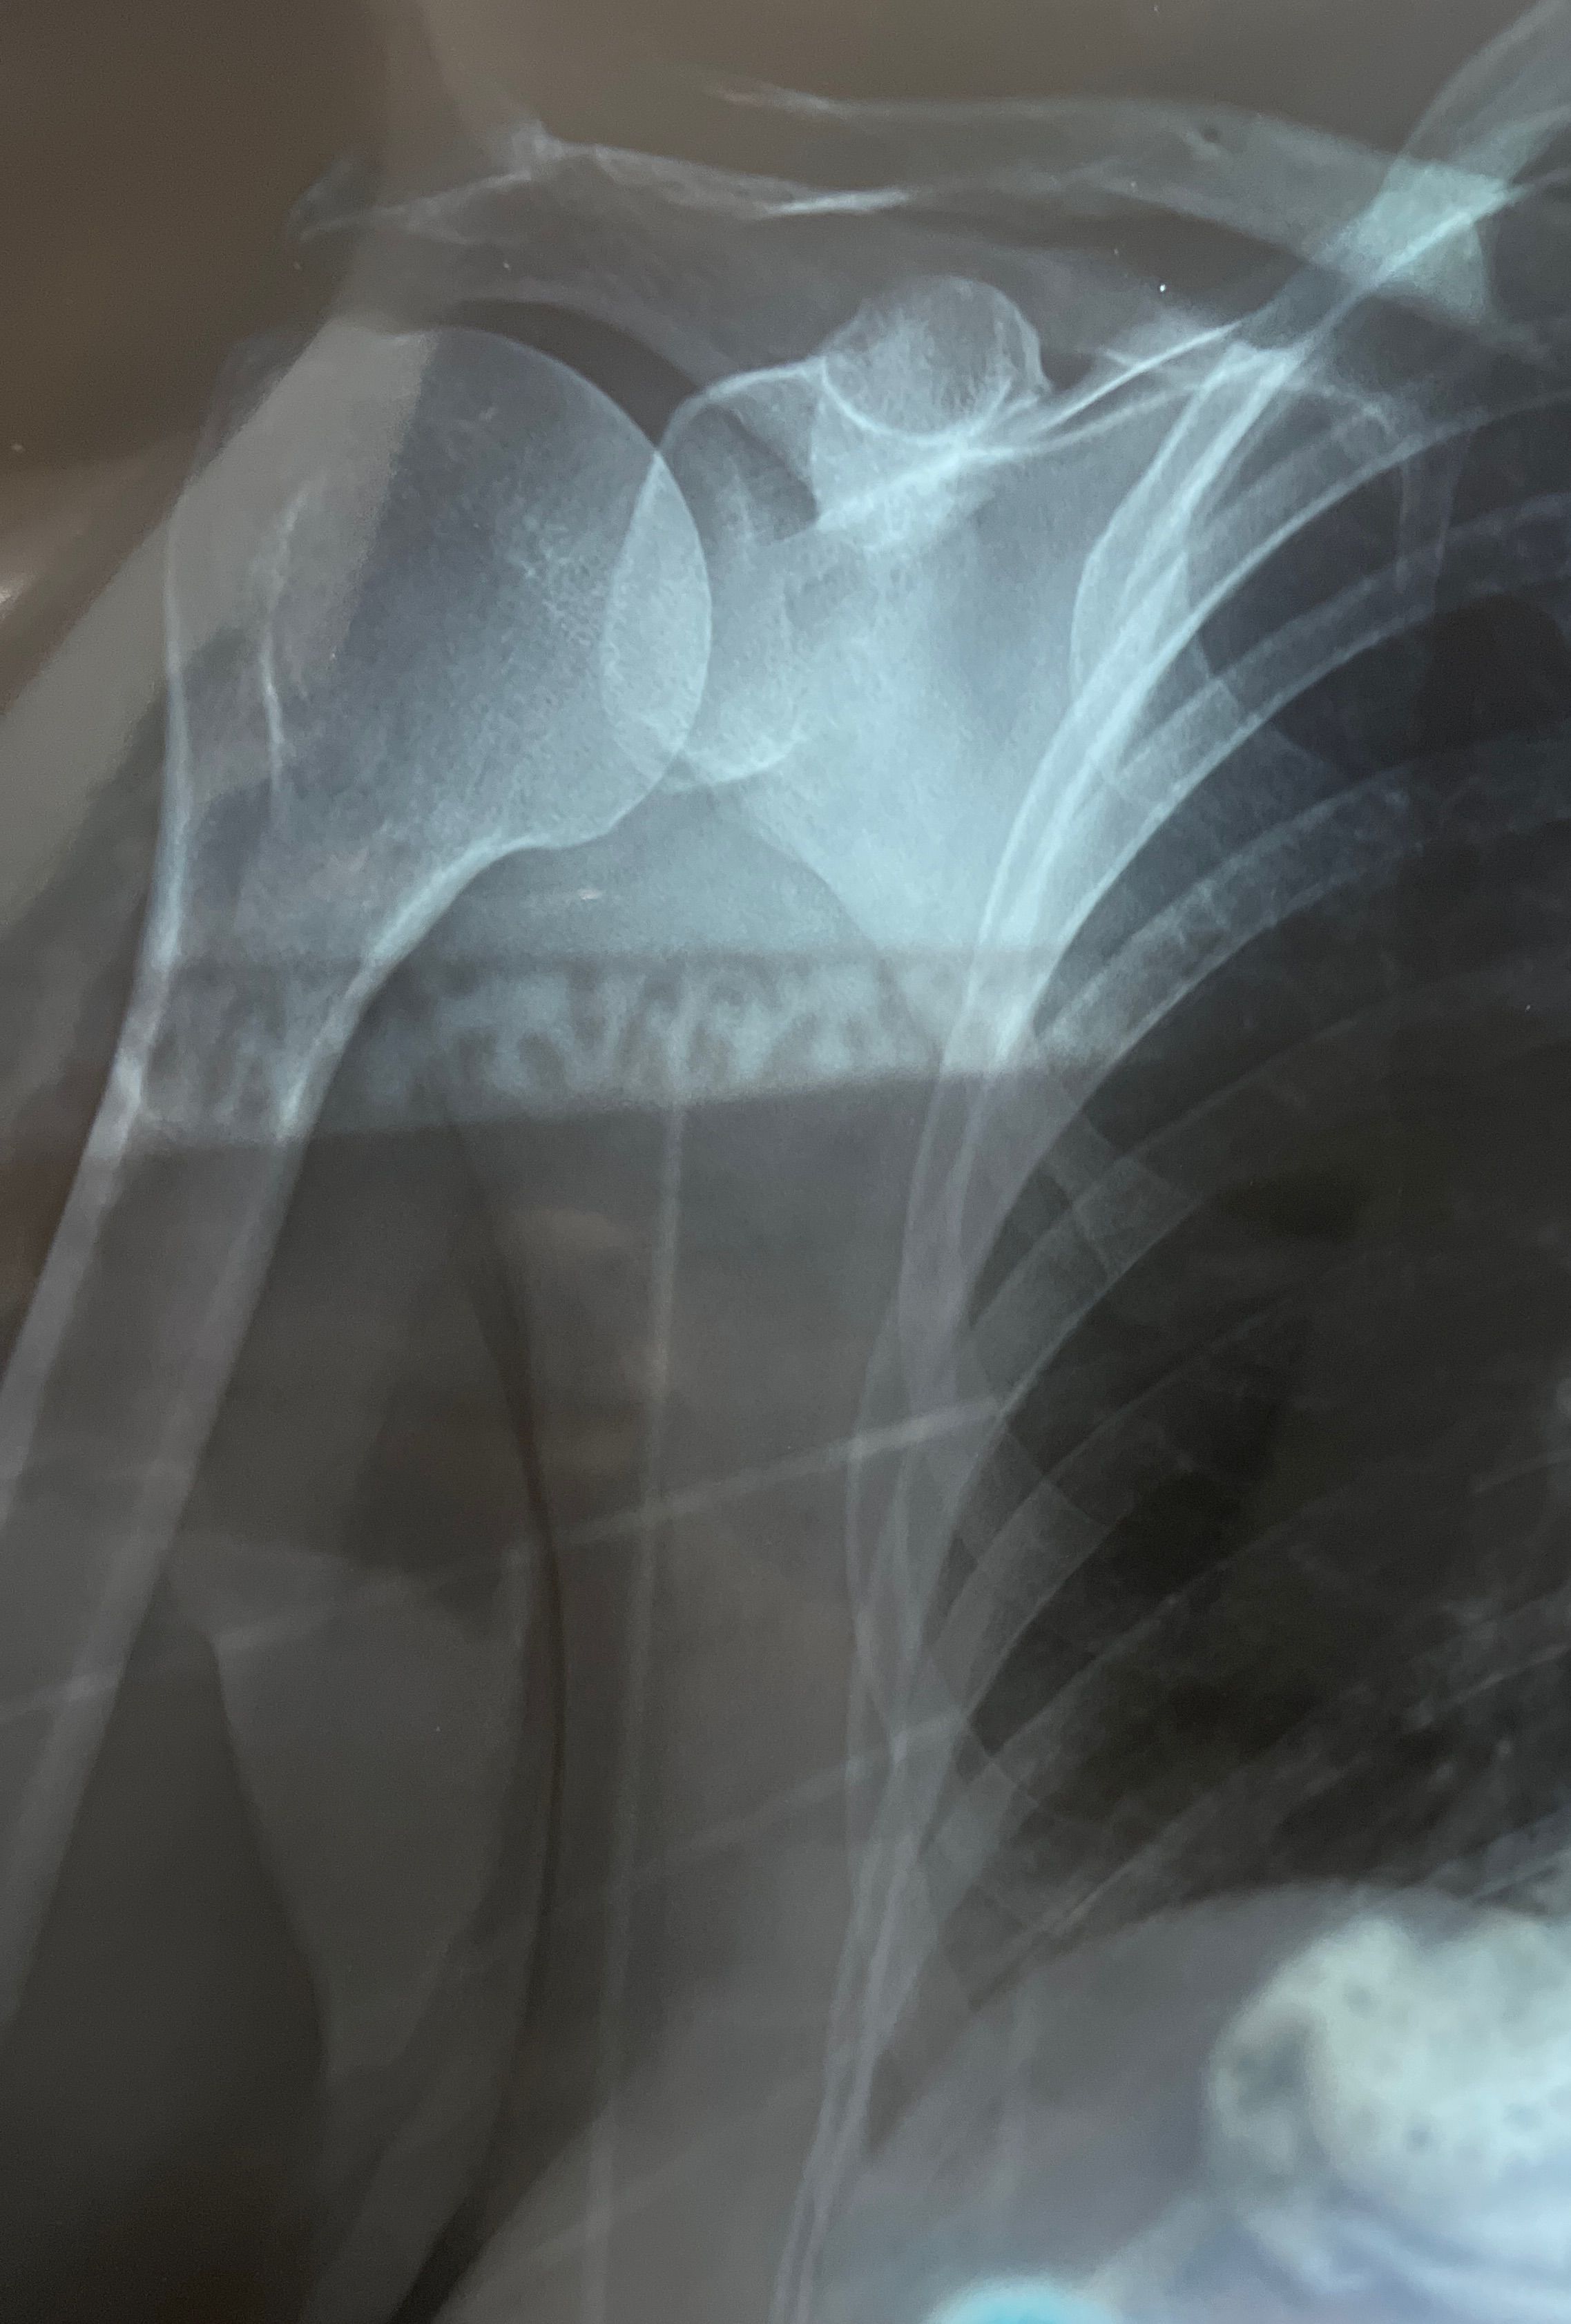

what’s this case???

Rt shoulder image

Bones

Joints

Osteoarthritis